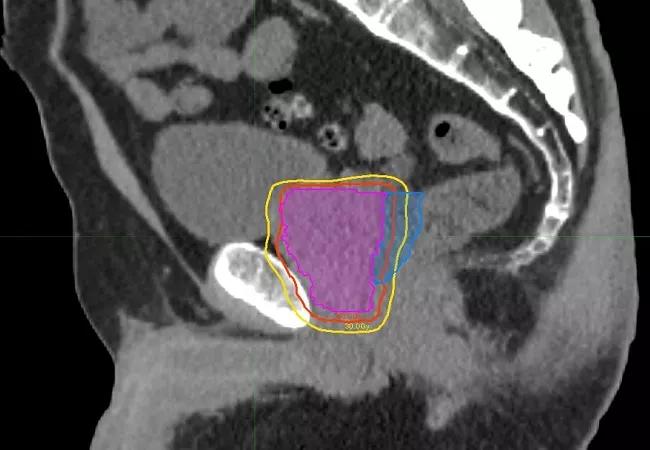

The etiology of radiation-induced erectile dysfunction is not precisely known, but may involve damage to the penile neurovascular bundles, crura and/or penile bulb. SAbR’s focused beam arrangements and immobilization during treatment potentially could reduce the volume of critical structures receiving high radiation doses, thus limiting or eliminating collateral damage. The POTEN-C trial will compare standard 40-50 Gy SAbR to SAbR with dose-painting intended to preserve functionality of critical neurovascular structures on at least one side of the pelvis by reducing dosage to 30 Gy.